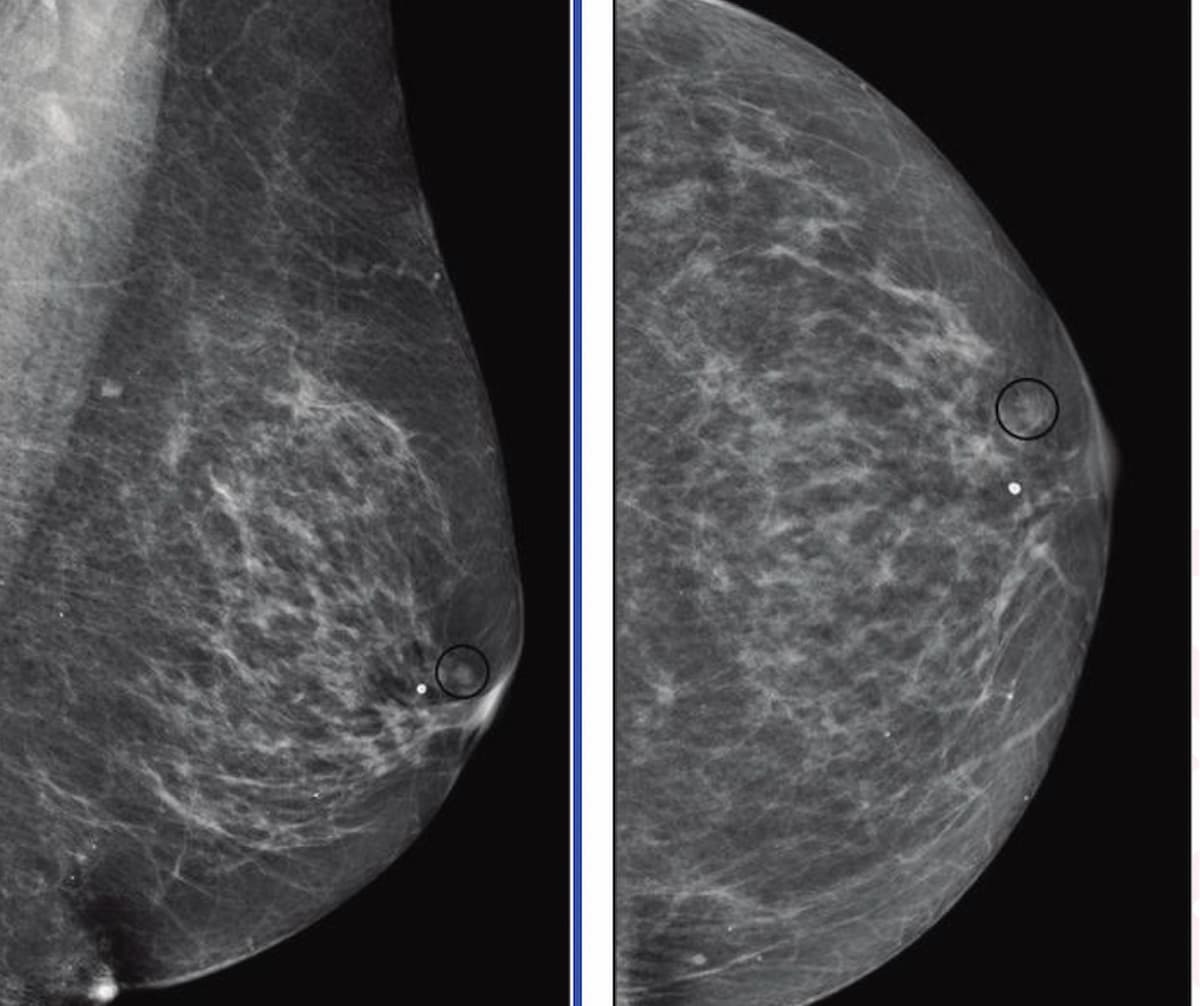

Researchers found that ChatGPT offered appropriate responses to 22 out of 25 patient-oriented questions on mammography screening, dense breasts, BI-RADS scoring and other topics related to breast cancer screening and prevention.